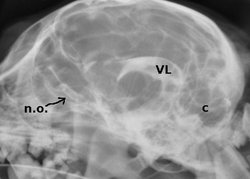

El líquido cefalorraquídeo, presente en el espacio subaracnoideo, nos permite visualizar, gracias al contraste que contiene, el aparato ventricular (VL: ventrículo lateral) además de los surcos cerebrales y cerebelares (c).